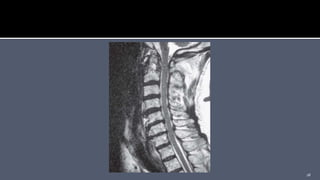

 Visualization of any soft tissue injuries (ligaments injury,

spinal cord injuries)

 Useful in rheumatoid patients (soft tissue pannus formation)

 MR Angiogram can be used to evaluate vertebral artery injury,

patency, and/or dominance.

 Visualization ofany soft tissue injuries (ligaments injury, spinal cord injuries)  Useful in rheumatoid patients (soft tissue pannus formation)  MR Angiogram can be used to evaluate vertebral artery injury, patency, and/or dominance. 17